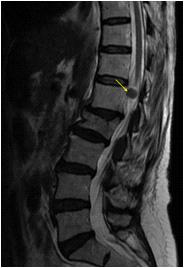

We found a strong positive correlation between abnormal EEG and abnormal Neuroimaging with Correlation coefficient of 0.902, (P- Value 0.0138) but almost no correlation found between normal EEG with normal Neuroimaging (Figs 1-4).

About 23% of patients with adult onset first seizure has metabolic derangement and the most common etiology was Dyselectrolytemia. The most common Central Nervous System (CNS) Infection as detected by CSF study was viral meningoencephalitis followed by Tuberculous Meningitis. The most common CNS lesion detected by CT studies as well as by MRI Brain was infarction and ring lesion, the two Neuroimaging studies corroborated in 75.38% of Seizure patients. Abnormal discharge in EEG found in34% cases. In majority patients EEG report was normal. EEG abnormality was more common in patients with Focal Seizure rather than GTCS patients. Thus, the most common etiology of first Seizure onset at adult age over 18 years were metabolic derangements (16.92%), CNS Infection or Inflammation (15.38%) and intracerebral Space occupying lesion (15.38%), usually ring lesion, tumors and Metastasis. Idiopathic Seizure found in 7.69% patients. The Correlation between abnormal Neuroimaging and abnormal EEG is strongly positive and statistically significant (P -Value = 0.013) but the same is not true in cases of normal Neuroimaging and normal EEG findings.